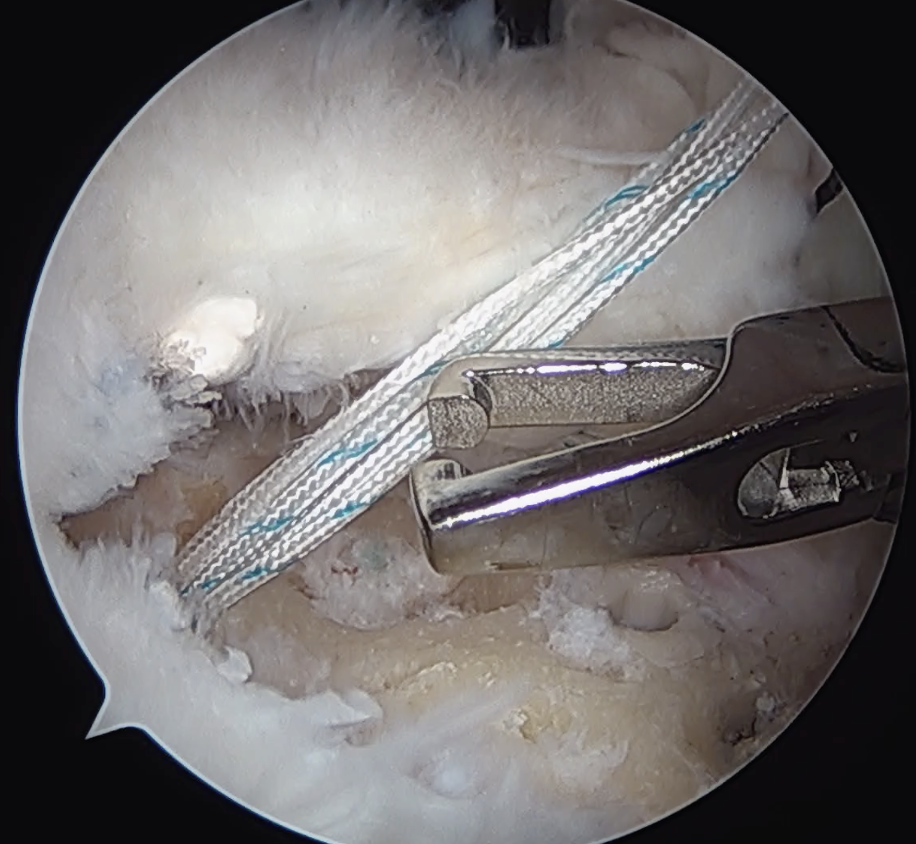

Pass sutures through medial cuff tendon

- camera posterior

- suture passer via lateral portal

- retrieve sutures through anterior portal

- repeat

- tie medial row

Double row / suture bridge

- use medial row sutures

- secure in knotless lateral row anchors